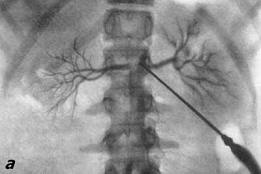

рентгено-контрастное вещество.Особым разделом специализированной

рентгенодиагностики являются различные виды ангиографии и лимфографии,

показывающие полный или частичный «блок» для прохождения контрастного вещества

в зоне злокачественной опухоли или метастатически пораженного лимфатического

узла.

Маммография ЭРПХГ

Почечная ангиография Лимфография